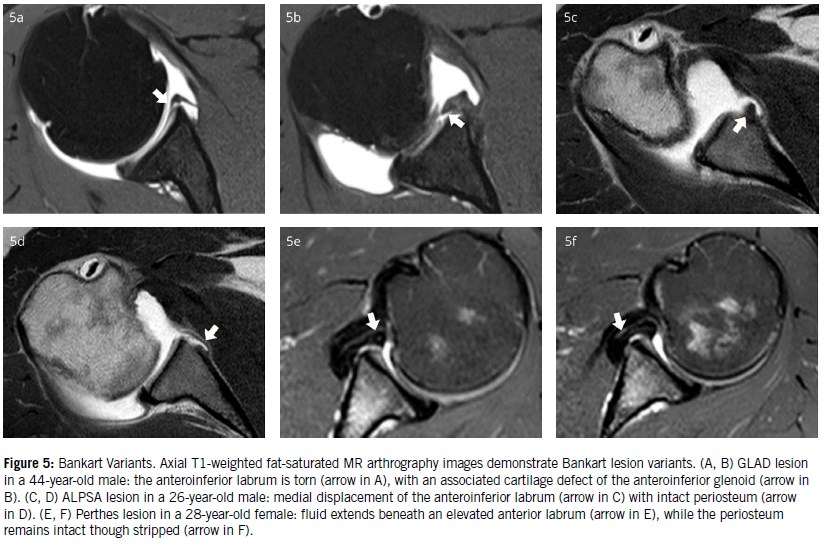

Several variants of the Bankart lesion exist (Figure 5):

• GLAD (glenolabral articular disruption): a superficial anteroinferior labral tear associated with adjacent cartilage damage.

• ALPSA (anterior labral periosteal sleeve avulsion): complete detachment with medial displacement and inferior rotation of the labrum. The periosteal stripping occurs, but there is no complete detachment.

• Perthes lesion: an avulsion of the anteroinferior labrum with a medially stripped yet intact periosteum. This lesion is best visualized in the ABER position, which places stress on the anterior band of the IGHL and anteroinferior capsule.